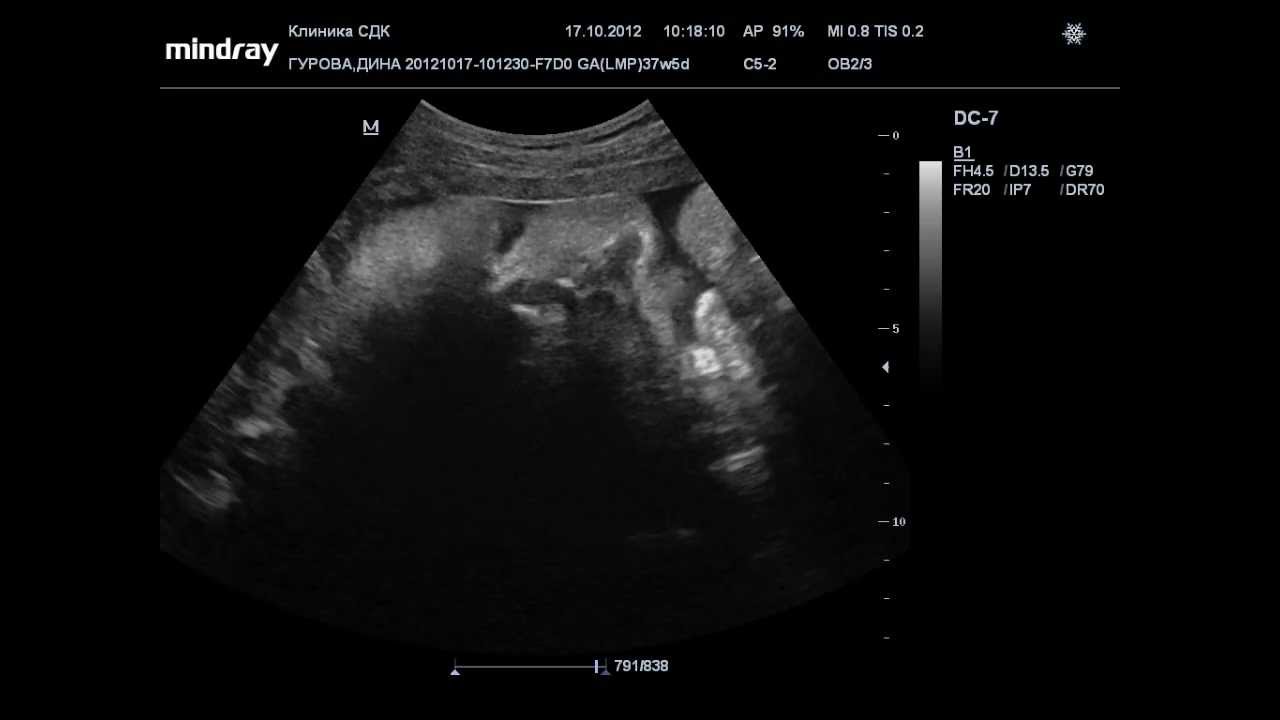

37 недель видео

37 недель видео 99 фото